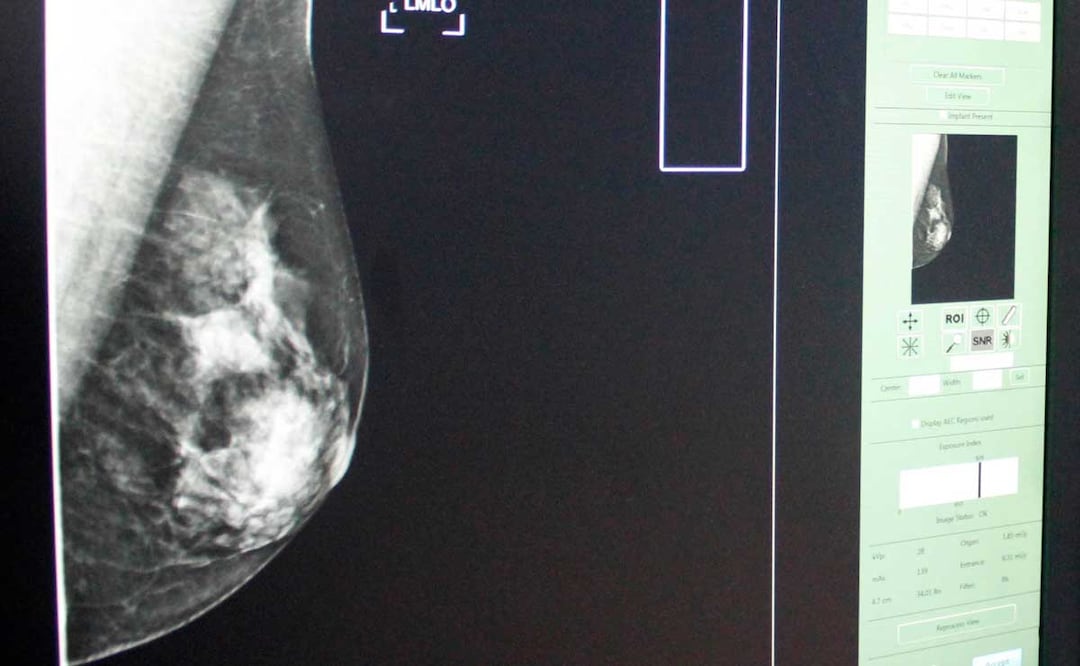

-Cáncer de mama